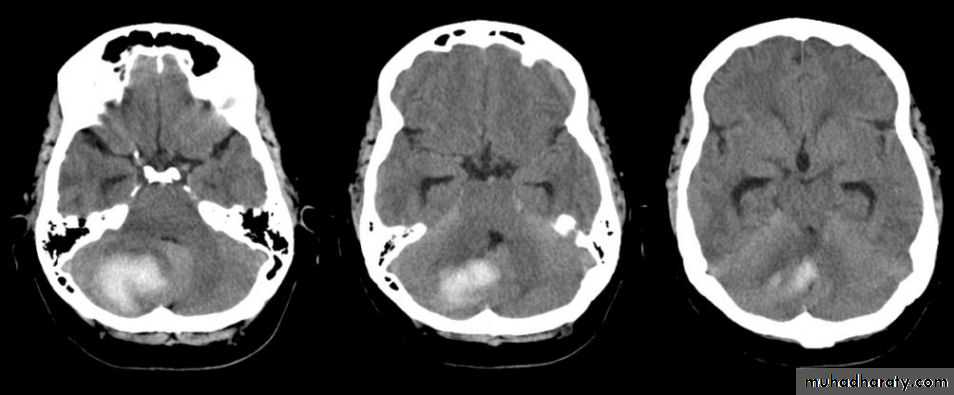

Cerebral haemorrhage:

• Haemorrhage is demonstrable on CT immediately after the event as a region of high attenuation

• Frequently causing mass effect.

• The initial high density of haemorrhage lessens over the following week or two leaving a low- density area indistinguishable from an infarct.

• May be associated with intraventricular or subarachnoid bleeding

Subarachnoid haemorrhage

• Usually due to a ruptured intracranial aneurysm or less commonly an arteriovenous malformation.• CT is the best initial investigation to diagnose.

• A subarachnoid haemorrhage is recognized by high density blood in the cortical sulci, Sylvian fissures and basal cisterns.

• CT will also show any intracerebral haemorrhage or blood in the ventricles